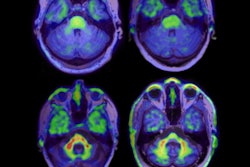

Over the last four years, AC Immune has received continuous grant support from the foundation to accelerate development of a-syn PET tracers. The goal is to develop a PET imaging tracer for clinical use that can accurately detect and monitor the progression of Parkinson's disease. An a-syn tracer also could enable and accelerate the development of Parkinson's disease therapies as a tool to measure the efficacy of drugs on the a-syn pathology in the brain.

Thus far, AC Immune's program has created multiple compounds designed to selectively bind with high-affinity to human Parkinson's brain-derived, pathological a-syn in preclinical studies. One a-syn PET tracer candidate entered clinical trials earlier this year -- also with the foundation's funding -- to image pathological a-syn in Parkinson's disease and other synucleinopathies.